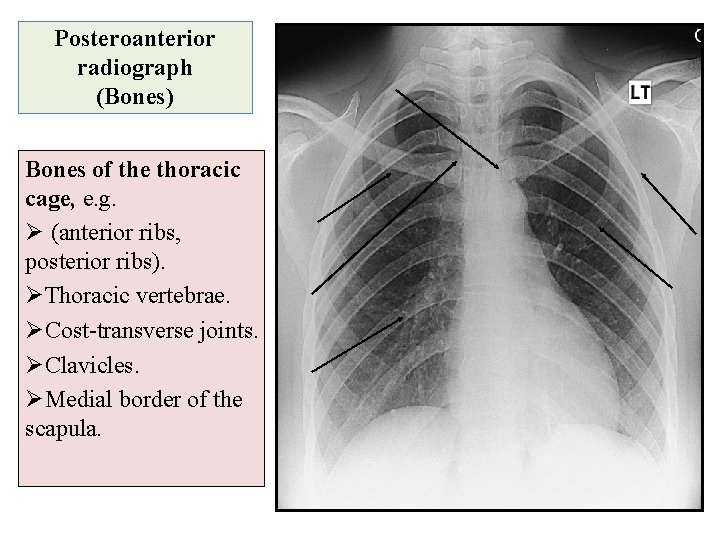

Posteroanterior radiograph (Bones) Bones of the thoracic cage, e. g. Ø (anterior ribs, posterior ribs). ØThoracic vertebrae. ØCost-transverse joints. ØClavicles. ØMedial border of the scapula.